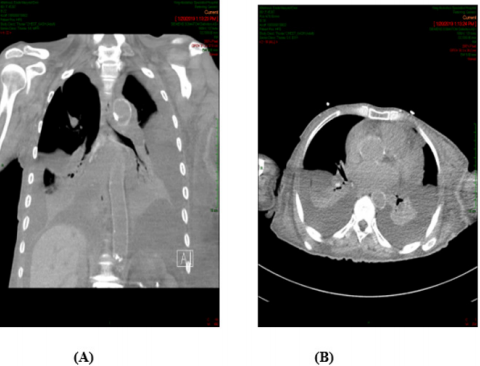

A 88-years old female with remarkable history for diabetes, ischemic heart disease, known case of CML for which she received imatinib for more than 10 years and still under treatment. This patient presented with two weeks history of gradually progressive breathlessness, mild cough associated with LL swelling and not associated with fever. The patient came to emergency department where ECG and echocardiography were normal apart from mild to moderate pericardial effusion, X-ray chest showed bilateral moderate pleural effusion (Figure 1) then patient was admitted for further evaluation and management. We asked for full investigations, CT chest showed moderate bilateral effusion more in the left side (Figure 2A) with mild pericardial effusion (Figure 2B), abdomino-pelvic ultrasound showed normal abdominal and pelvic organs with moderate free fluid in abdomen and pelvis, complete blood count, renal function tests, liver function tests and serum electrolytes are all within normal limits. Aspiration of both ascetic and pleural fluids was done and subjected to chemical, microbiological and cytological analysis which showed features of transudate with no growth of any organism. So based on history, clinical examination and investigations, all causes of generalized edema were excluded and the only explanation for development of this generalized FR was imatinib use. As the patient was in hematological and molecular complete response(CR) for last year, we stopped the imatinib and the patient was followed and treated symptomatically. We expected that the conditions of the patient will improved after imatinib withdrawal and diuretics, but there is no improvement after more than 3 weeks of stoppage of imatinib.

Figure 2: (A): CT chest showed bilateral pleural effusion more in the Lt side, (B): With minimal pericardial effusion.